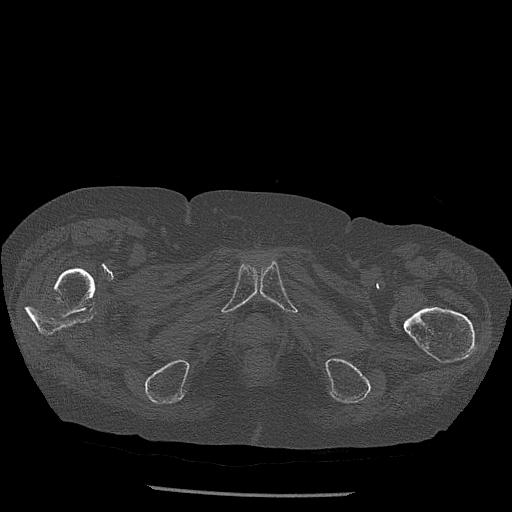

100703 1/27 両股正面+軸 1/29 両股正面+軸 94歳女性 パンソンロン